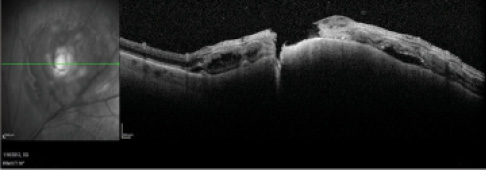

Figure 1. Small malignant melanoma with significant orange pigment and exudative retinal detachment.

Treatment of small uveal malignant melanoma (Figure 1) is controversial. GEP allows prognostication for small uveal melanomas with minimal surgical risk (Figures 2 and 3). This technology affords clinicians the opportunity to treat earlier in the disease process, thereby minimizing the likelihood of metastatic spread.